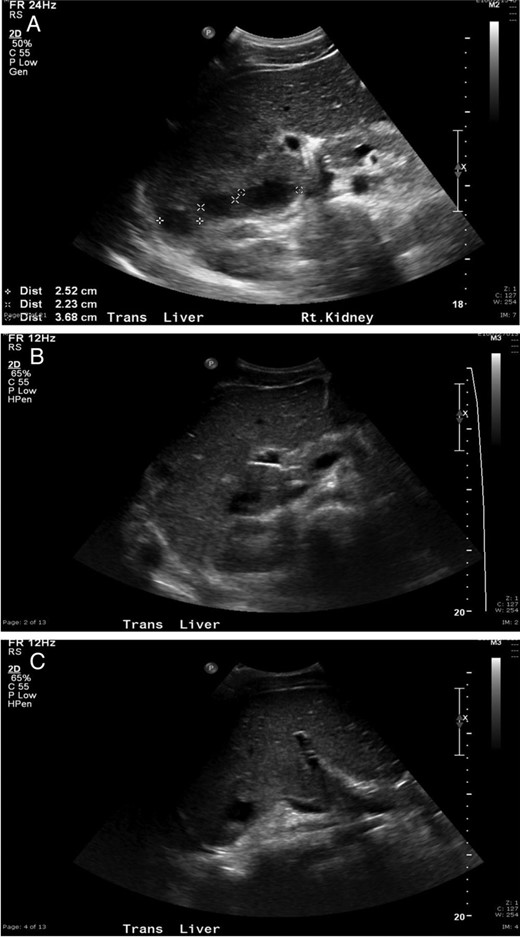

The patient was started on broad-spectrum antibiotics and underwent ultrasound-guided percutaneous drainage of the largest hepatic abscess, which measured 5 cm (Fig. 2A). The aspiration cultures grew Fusobacterium necrophorum. Despite directed antibiotic therapy, the patient developed worsening tachypnea, fevers, abdominal pain and leukocytosis. A repeat abdominal ultrasound showed an increase in the size of the hepatic abscess. Two additional drainage procedures were performed on hospital Days 7 and 9, which ultimately drained 15 of the collections and removed >120 ml of purulent fluid (Fig. 2B and C). No organisms grew from cultures of the subsequent hepatic aspirations, and the patient demonstrated significant clinical improvement with resolution of pain and fever. Repeat ultrasound on hospital Day 12 showed complete resolution of most hepatic abscesses with no new focal lesions. Antibiotic coverage was further narrowed, and the patient was discharged on a 6-week total course of antibiotics. At the time of this report, the patient continues to do well at home.

(A) Ultrasonography following initial drainage showing several residual abscesses within the liver, but decreased in number compared with prior exam. (B and C) Ultrasound demonstrating interval improvement in the multiple liver abscesses, with the majority becoming smaller in size and some demonstrating complete resolution.